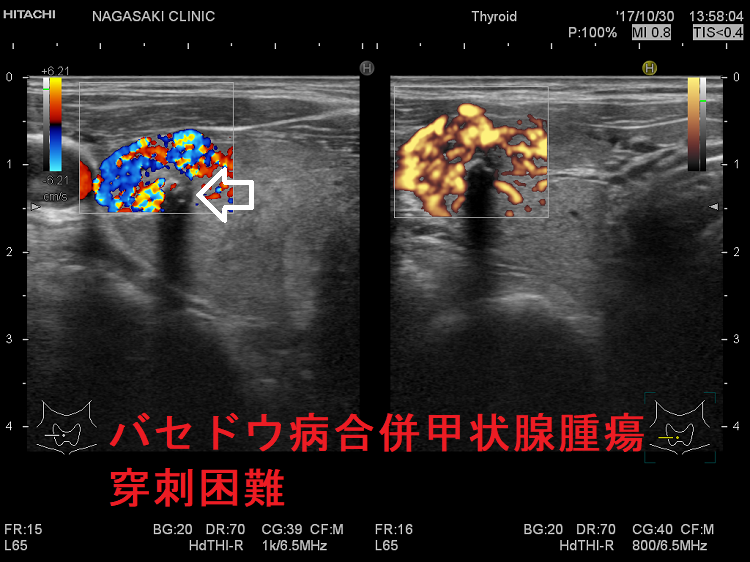

甲状腺穿刺細胞診の主な有害事象の一つは穿刺時出血、穿刺後出血;最悪、気道閉塞により窒息。注意しても唾を飲む方におこる。用手圧迫、再度、超音波エコー、造影CT、喉頭ファイバー行い出血・喉頭腫大を確認後入院。甲状腺機能亢進症/バセドウ病、TSH高値の重度甲状腺機能低下症は甲状腺内部血流が異常増加し穿刺で大出血の危険。甲状腺ホルモン正常化し血流低下を待つ。頚動脈に接する・連鎖して拍動する、下甲状腺動脈直下の小さな甲状腺腫瘍は穿刺難。甲状腺血管腫は何度穿刺細胞診しても血液成分のみで穿刺後出血の危険。最下甲状腺動脈穿刺で大出血。

穿刺細胞診するには、あまりにリスクが大きく、断念せざる得ない場合があります。たとえば、

- 頚動脈に接する小さな甲状腺腫瘍

- 頚動脈近傍で、頸動脈に連鎖して拍動する小さな甲状腺腫瘍

- 下甲状腺動脈直下で穿刺困難の小さな甲状腺腫瘍

甲状腺乳頭癌の可能性があるため、穿刺細胞診したくても、頚動脈や気管を刺してしまう危険を考えれば断念するのが正しいと思います。「退く勇気」も大切なのです。その代わり、甲状腺腫瘍が大きくならないか、腫瘍マーカーは上昇しないか、定期的に経過を見る必要があります。